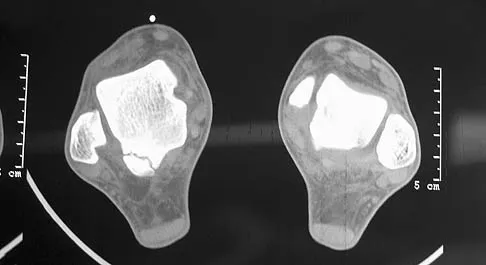

A 10-year-old boy has had a prominent scapula for the past year. He reports crepitus and aching over the area, but only when he is active. A radiograph and CT scans are shown in Figures 37a through 37c. What is the most likely diagnosis?